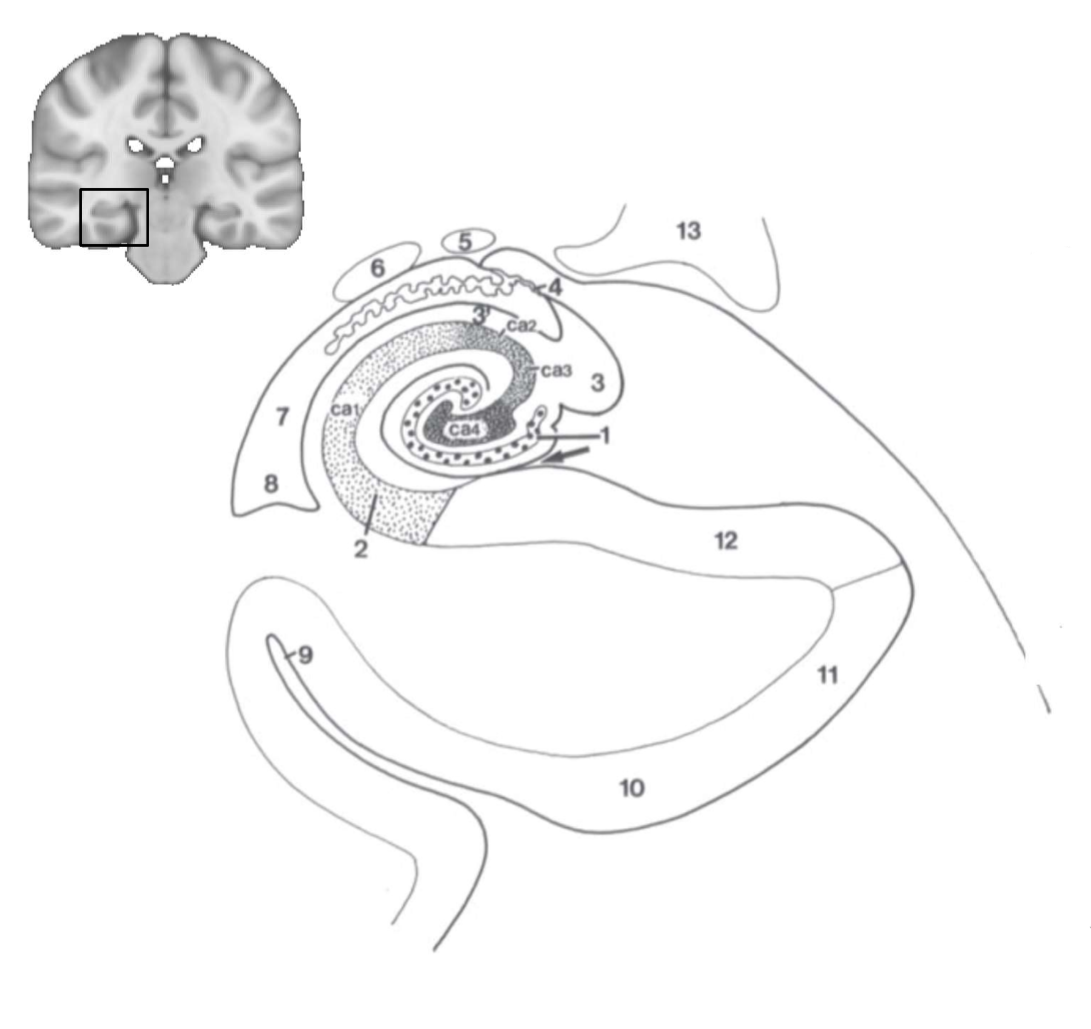

What structure is this?

hippocampus

What is 1?

hippocampus

What is 2?

rhinal sulcus

What is 3?

lateral ventricle

What is 4?

thalamus

What is 5?

entorhinal cortex

What is 6?

perirhinal cortex

What is 7?

parahippocampal cortex

What is 1?

gyrus dentatus

What is 2?

cornu ammonis

What is 3?

fimbria

What is 3’?

alveus

What is the arrow pointing to?

happicampal sulcus

What is ca1, ca2, ca3 and ca4?

fields of cornu ammonis

What is 4?

tela choroidea

What is 5?

stria terminalis

What is 6?

tail of caudate nucleus

What is 7?

temporal horn of lateral ventricle

What is 8?

collateral eminence

What is 9?

collateral sulcus

What is 10?

parahippocampal

What is 11?

entorhinal area

What is 12?

subiculum

What is 13?

lateral geniculate body